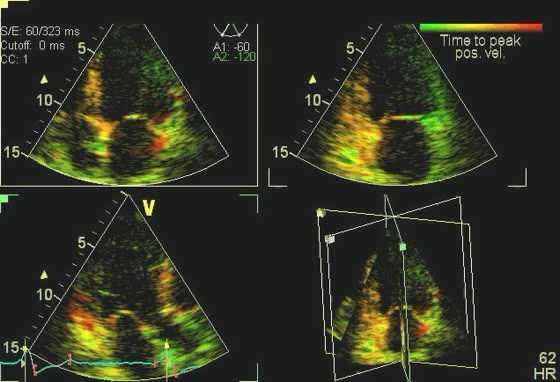

Диастолическая функция у спортсменов на ЭхоКГ

Спортсмены показывают нормальные или сверхнормальные показатели диастолической функции на ЭхоКГ, тогда как аномальное расслабление миокарда считается признаком ГКМП. Как и в случае со всеми другими аспектами этой болезни, паттерн наполнения миокарда колеблется от нормального у одних людей до серьезных нарушений у других. Различные параметры диастолической функции могут быть полезны для различения физиологической ГЛЖ и ГКМП, включая скорость притока ЛЖ, время замедления волны E, время изоволюметрической релаксации, тканевый допплер e ', соотношение E / e' и допплеровский кровоток в легочных венах. Спортсмены демонстрируют нормальные паттерны наполнения митрального клапана и нормальное соотношение E: A.

Используя тканевую допплерографию с импульсной волной для оценки скорости латерального кольца ЛЖ, спортсмены имеют нормальные или высокие значения e ', обычно значительно превышающие 10 см / с. Отношение E / e 'менее 8 также свидетельствует о нормальной физиологии сердечной мышцы. Измерения, проведенные рядом с медиальным кольцом митрального клапана, по-видимому, менее воспроизводимы при наблюдении за этим полезным эхокардиографическим открытием. Важно подчеркнуть, что, хотя все эти параметры полезны для диагностики ГКМП в крупных когортных исследованиях, их отсутствие достоверно не исключает ГКМП у спортсменов. Действительно, наш опыт показывает, что у большинства спортсменов (90%) с выявленной гипертрофической кардиомиопатией латеральное значение e '> 9 см / с, а у 92% - E / e'

Систолическая функция у спортсменов на эхокардиографии

У спортсменов на ЭхоКГ регистрируется нормальная систолическая функция, а у некоторых спортсменов на выносливость может наблюдаться погранично низкая фракция выброса из-за большой полости ЛЖ и брадикардии в покое. Напротив, люди с ГКМП имеют обычно высокую фракцию выброса и частичное сниженное укорочение, потому что у них обычно небольшая полость ЛЖ. Однако при оценке систолических кольцевых (S a) скоростей с помощью импульсно-волнового тканевого допплера большинство пациентов с ГКМП имеют низкие скорости ниже 10 см/с.

У спортсменов на эхокардиографии регистрируют гораздо более высокие значения, обычно значительно выше 10 см/с. Тканевые допплеровские исследования продольной деформации показывают, что спортсмены с физиологической ГЛЖ демонстрируют нормальные гомогенные паттерны деформации, тогда как пациенты с ГКМП имеют низкую и гетерогенную картину деформации. Исследование пациентов с ГКМП, спортсменов и здоровых людей из контрольной группы показало, что глобальная продольная деформация